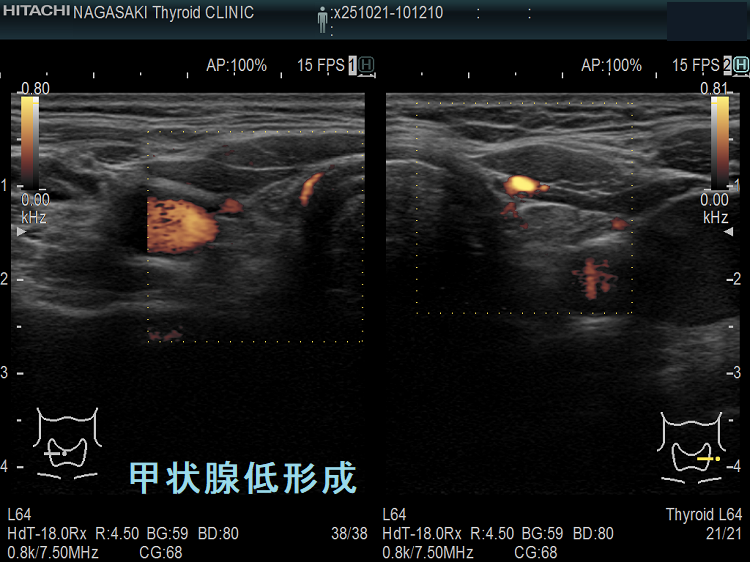

先天性甲状腺機能低下症(クレチン症)の内、甲状腺形成障害の割合は約40%です[無形成3%、低形成16%、異所性22%]。

![甲状腺低形成(橋本病合併)[垂直断] 甲状腺低形成(橋本病合併)[垂直断]](../images/special/thyroid4/images20231217223003.png)